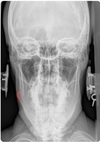

NASIUM ANATOMICAL LANDMARKS

upper teeth

54

medial inferior tip of condyle

55

Nasium view

nasal septum + spine

56

transverse process of c1-c3

57

lower teeth

58

spinous process c2-t1

59

nasal aperture

60

maxillary sinus

61

frontal sinus

62

mastoid (air cells) process

63

lateral mass c1

64

occipital-atlantal joint space

65

atlantal-axial joint space

66

mandible body

67

mandible ramus

68

mandible angle

69

mandible mentum

70

odontoid process

71

articular pillar